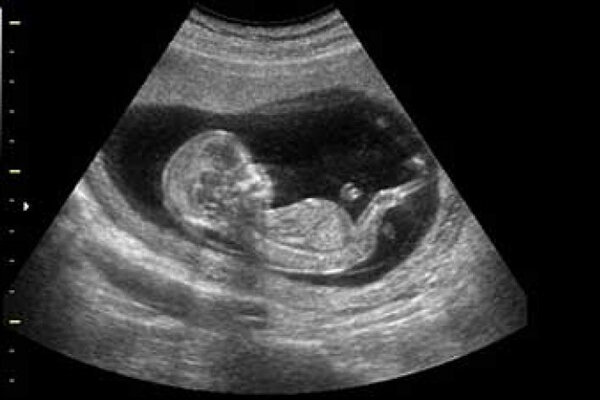

کارگردان «جادههای برقی» در توضیح این مساله که چرا سونوگرافی باعث افزایش تعداد نوزادان پسر شده است، بیان کرد: خانوادههایی که به دنیا آمدن فرزند پسر برایشان بسیار مهم است، وقتی در سه ماهگی یا ۲ ماهگی متوجه جنسیت جنین دختر خود میشوند، به راحتی به سمت سقط میروند یا از طریق رژیم غذایی، تزریق آمپول یا کاشت تخمک به پسر شدن فرزندشان کمک میکنند. این مستند موضوعمحور به تعیین جنسیتی اشاره میکند که به دست بشر افتاده و عامل نابود شدن موازنه جنس جنین در جهان است.

وی تاکید کرد: در این مستند قرار بود یک زن حضور داشته باشد؛ او برای تعیین جنسیت فرزند پسرش به پزشک مراجعه میکرد، من از ابتدای تصمیم او برای گرفتن رژیم غذایی مناسب، انجام سونوگرافیها و خرید داروها با او همراه شدم و تمام هزینههای معالجهاش را برعهده گرفتم به شرطی که با ما در طول ساخت مستند همراه باشد اما به دلیل مخالفت همسرش، بعد از سه ماه از همراهی با پروژه منع شد تا اگر نوزاد دختر باردار بود، بدون دخالت هر کسی آن را سقط کند.